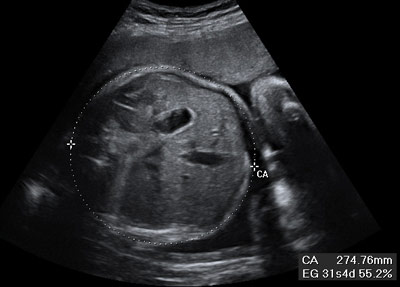

Ecografía: Medición del perímetro abdominal

Es el contorno por encima del ombligo fetal

Ecografía de la medición del perímetro del abdomen fetal en el tercer trimestre de embarazo

Corresponde al contorno del abdomen fetal ligeramente por encima del ombligo. En esta imagen podemos ver con claridad ese perímetro, enmarcado en el círculo blanco.